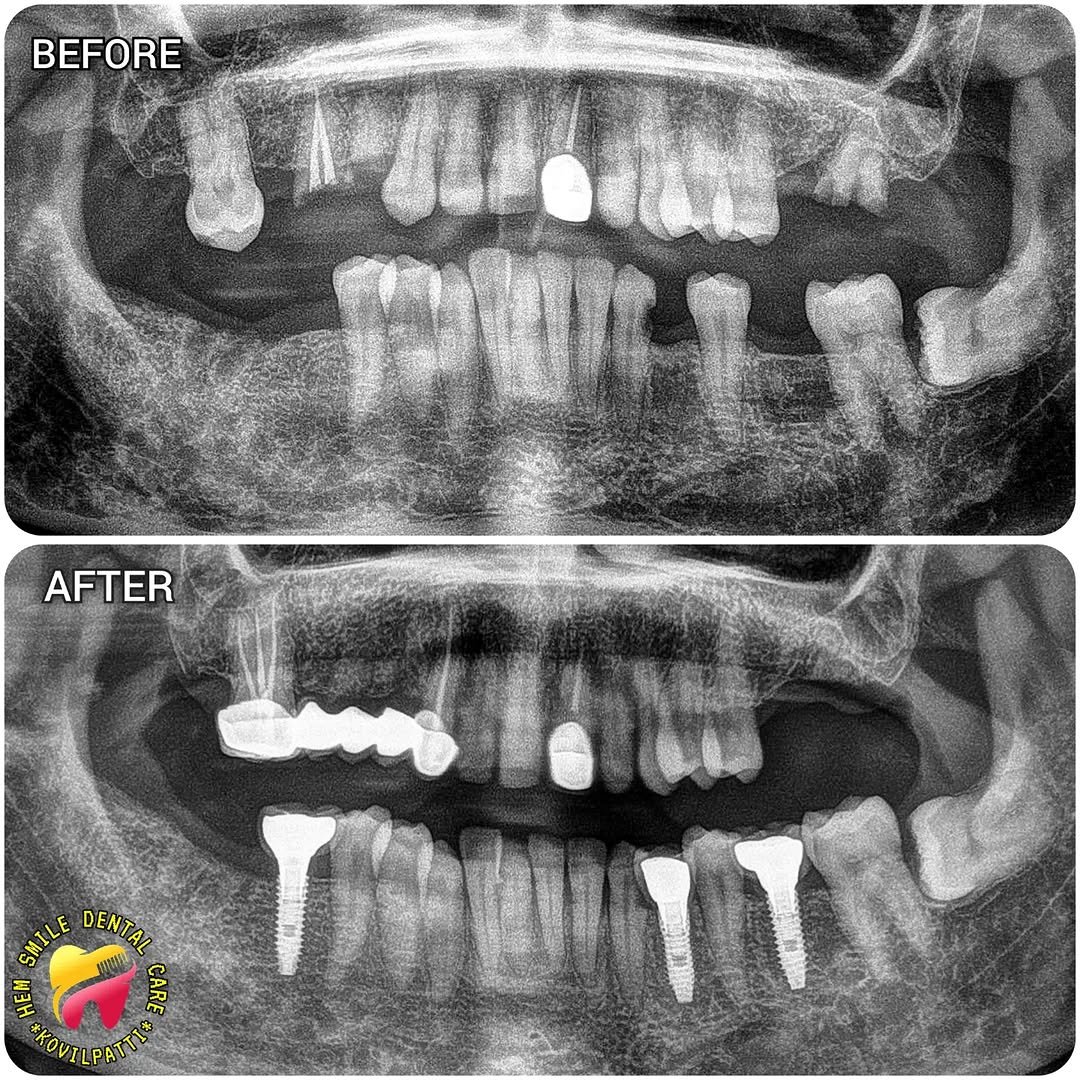

Transformations We’ve Crafted

A glimpse of our successful treatments and happy smiles at Hem Smile Dental Care.

Full Mouth Dental Implant